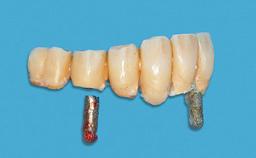

Four Immediately Loaded Mini-Implants Supporting a Mandibular Overdenture

# of Implants 4

Type of Implants One-Piece|Reduced-Diameter

Attachment One-Piece|Reduced-Diameter

Prosthesis Type RDP